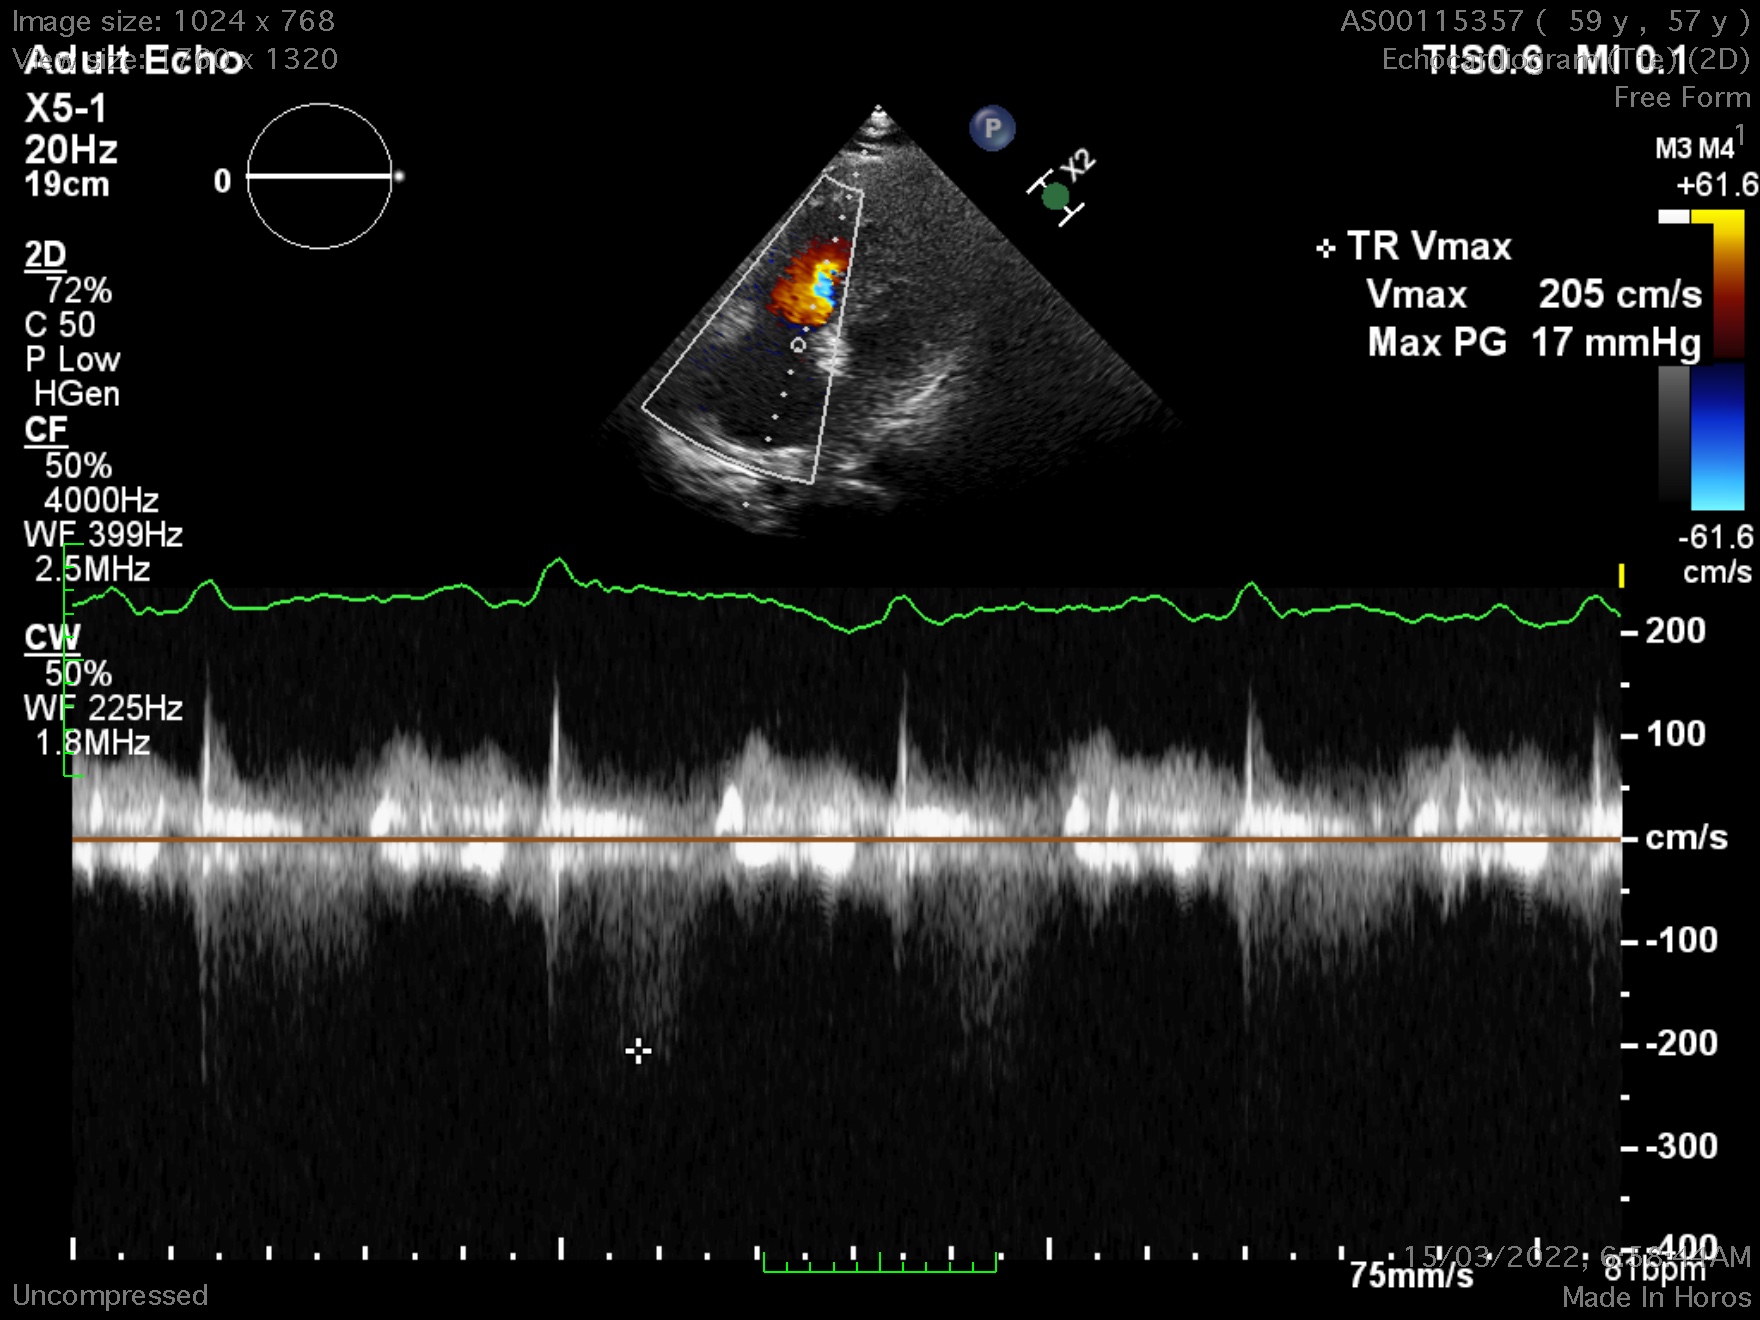

First, a trans-thoracic echocardiography(TTE) was done, there is a defect over the intra-atrial septum (IAS) with a dilated right heart. The doppler study exhibited a left to right shunting. A trans-oesophageal echocardiography (TOE) was done to assess the IAS & he has a secundum atrial septal defect(ASD), with anterior wall deficits but preserved inferoposterior wall length, largest diameter measuring 38.7mm. Estimated pulmonary arterial systolic pressure was 17 + 3 mmHG.